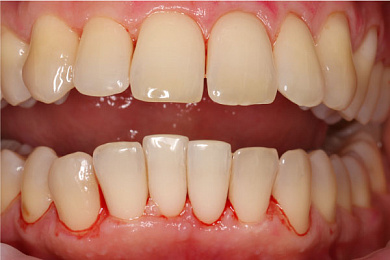

- Затем проводится удаление мягкого налёта аэрозольным методом: зубы обрабатываются составом: вода с мельчайшими абразивными частицами бережно очищает поверхность зубов от налёта. Благодаря этой процедуре зубы становятся светлее сразу на 1-2 тона.

Результат лечения